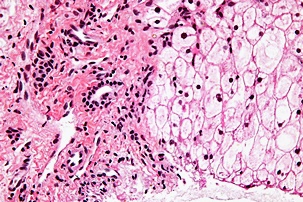

황달이 생기는 이유는 담즙색소라고 알려진 빌리루빈이 과도하게 생기기 때문입니다. 빌리루빈은 우리 몸의 오래된 적혈구가 파괴되면서 생기는 물질인데요. 이 물질은 담즙에 녹아서 우리 몸의 배설물과 함께 배출이 되는 것이 정상적이지만 빌리루빈의 과잉생산이나, 간의 장애, 간세포나 담도의 손상에 의해 빌리루빈이 역류할 경우 발생된다고 합니다.

황달이 생겼을 때 나타나는 대표적인 증상은 소변의 색깔이 진하게 변하는 것입니다. 이는 과도하게 분비된 빌리루빈이 소변으로 배출되기 때문인데요. 이러한 경우 소변의 색이 진한 갈색으로 변하게 됩니다. 또한 피부에 담즙색소가 침착되면 눈이 노랗게 변하는데요. 눈에 노랗게 된다고 모두 황달 증상을 의심할 수 있는 것은 아닙니다.

보통 눈과 피부, 소변의 색깔에 모두 이상이 생긴 경우 황달 증상으로 볼 수 있으며 병원에 내원하여 진단을 받아보는 것이 권장됩니다. 황달이 생기는 경우 피부 가려움증을 동반한다고 하는데요. 이러한 이유는 배출되어야 할 화학물질이 피부의 신경조직을 자극하여 발생한다고 추측하고 있습니다.